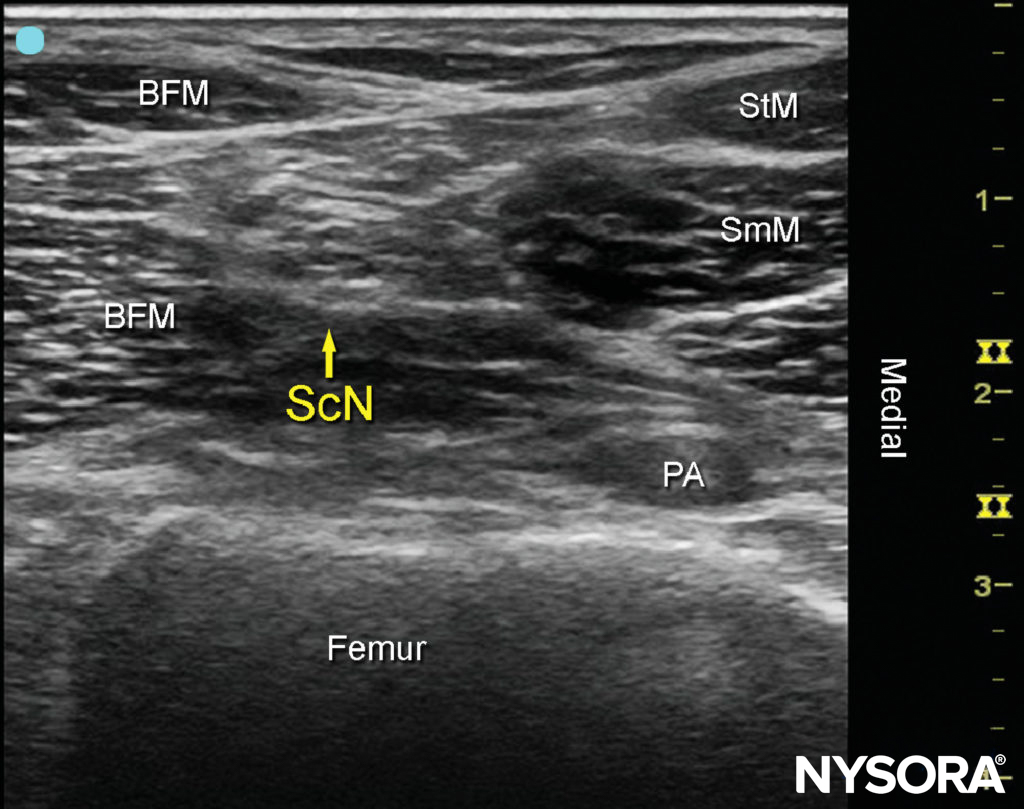

Once the tibial nerve has been identified, the CPN is visualized slightly more superficial and lateral to the tibial nerve. The transducer should be slid proximally until the tibial and peroneal nerves are visualized coming together to form the sciatic nerve before its division (Figure 4). This junction usually occurs at a distance 5–10 cm from the popliteal crease but may occur very close to the crease or, less commonly, more proximally in the thigh.

FIGURE 4 Sonoanatomy of the sciatic nerve (ScN) before its division. Shown are the ScN, superior and lateral to the popliteal artery (PA), positioned between the biceps femoris muscle (BFM) the semimembranosus muscle (SmM), and the semitendinosus muscle (StM).

As the transducer is moved proximally, the popliteal vessels move deeper and become more challenging to image. Adjustments in depth, gain, focus, and direction of the US beam should be made to keep the nerve visible at all times. At the popliteal fossa, the sciatic nerve typically is visualized at a depth of 2–4 cm.